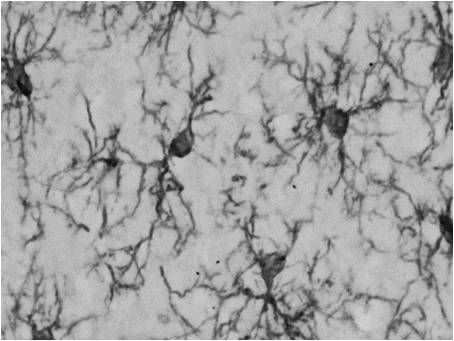

Iba1是在小胶质细胞和巨噬细胞中高度表达的蛋白质,分子量约17 kDa。 此蛋白质通常称为中枢神经系统中的小胶质细胞标记物。 最近,小胶质细胞已被广泛研究,其负责中枢神经系统中的免疫功能,并且与各种疾病相关,如神经变性疾病,精神错乱,脑肿瘤和感染。 |

◆应用 - 免疫组织化学染色

→使用抗Iba1,单克隆抗体(FUJIFILM Wako产品编号:012-26723)小胶质细胞的定位信号清晰,与抗Iba1,兔多克隆抗体的效果相同(FUJIFILM Wako产品编号:019-19741、019-19741)。

◆实验条件

● 样品:7周龄大鼠,7周龄小鼠或成年狨猴的大脑皮质

● 切片:50 μm冰冻切片(小鼠和大鼠),40 μm冰冻切片(狨猴)

● 染色法:ABC法+DAB染色

● 抗体浓度= 1:500